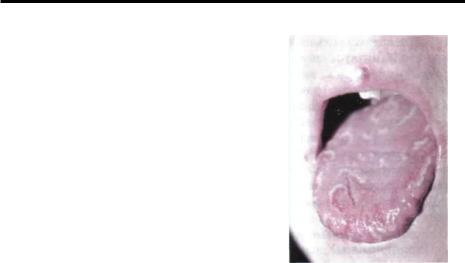

Поражение языка при псориазенередкое явление (рис.7-9). Вот как описывает его в 1901 г А.И.Поспелов: "Псориатические бляшки были приподняты над уровнем слизистой оболочки, окружены тонкими красно-фиолетового цвета

ободками, имели серовато-мато- Рис.7-9: Псориаз языка. вый цвет и как бы слегка были исколоты иглой, чем резко отличались отлейкоплакии".

Однако, высыпания чаще локализуются на слизистой оболочке щёк, нежели на языке. В последнем случае они располагаются на слегка гиперемированном основании, почти не возвышаясь над уровнем слизистой оболочки, покрыты рыхлым беловатосерым налётом, легко удаляющимся, после чего обнажается *»-слегка кровоточащее пятно красного цвета. Бляшки имеют размер1-1,5 см, не серпигинируют и не проявляют тендеции к разрешению или миграции.